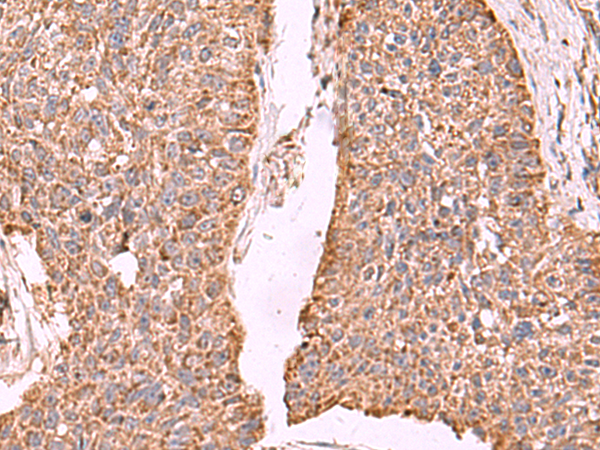

分类: 科研抗体货号: P10126别名: p40; RAB9P40; bA65N13.1应用: IHC反应种属: Human